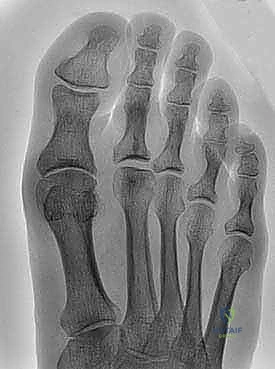

Radiographic evaluation includes weight-bearing anteroposterior, lateral, and oblique views to assess joint space narrowing, osteophyte size, subchondral sclerosis, and alignment.

Radiographic image demonstrating significant dorsal osteophyte formation in hallux rigidus.

Radiographic Imaging Protocol

Standard weight-bearing radiographs are essential for assessing the severity of hallux rigidus and guiding surgical planning.

* Weight-bearing Anteroposterior (AP) View: Evaluates joint space narrowing, metatarsophalangeal angle, hallux interphalangeal angle, and identifies medial and lateral osteophytes.

* Weight-bearing Lateral View: Crucial for assessing the size and location of dorsal osteophytes, degree of joint space narrowing, and presence of metatarsus primus elevatus. This view best demonstrates the extent of dorsal impingement.

* Oblique View: Helps visualize the articular surface and presence of osteophytes that may be obscured on other views.

The Coughlin and Shurnas classification system (Grades 0-4) provides a framework for interpreting radiographic findings and correlating them with clinical severity. Advanced imaging such as CT or MRI is generally not required for routine cheilectomy unless there is suspicion of other pathologies (e.g., osteochondral lesions, stress fractures, or soft tissue masses) or for detailed preoperative planning in complex cases.

Radiographic image displaying advanced hallux rigidus with significant joint space narrowing and dorsal osteophytes, indicating careful consideration for cheilectomy.